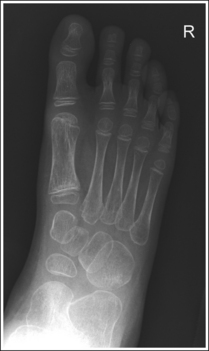

See Figure 6-12 and Box 6-5.

The foot demonstrates an AP projection. The joint space between the medial (first) and intermediate (second) cuneiforms is open, approximately 0.75 inch (2 cm) of the calcaneus is demonstrated without talar superimposition, and concavity on both sides of the first metatarsal midshaft is equal.

• An AP projection of the foot is obtained by flexing the supine patient's knee and placing the plantar foot surface against the IR (Figure 6-14). The lower leg, ankle, and foot should remain aligned, and equal pressure should be applied across the plantar surface.

• Effect of foot rotation. If the lower leg, ankle, and foot are not aligned or if more pressure is placed on the medial or lateral plantar surface, foot rotation will result, and the medial and intermediate cuneiform joint space will be closed. When the foot is laterally rotated, the navicular tuberosity, which superimposes itself on an AP projection, is rolled into profile, and the talus moves over the calcaneus, resulting in less than 0.75 inch (2 cm) of calcaneal demonstration without talar superimposition. An increase in metatarsal base superimposition also occurs (see Images 11 and 12). When the foot is medially rotated, the talus moves away from the calcaneus, resulting in more than 0.75 inch (2 cm) calcaneal visualization without talar superimposition. A decrease in superimposition of the metatarsal bases also occurs (see Image 13).